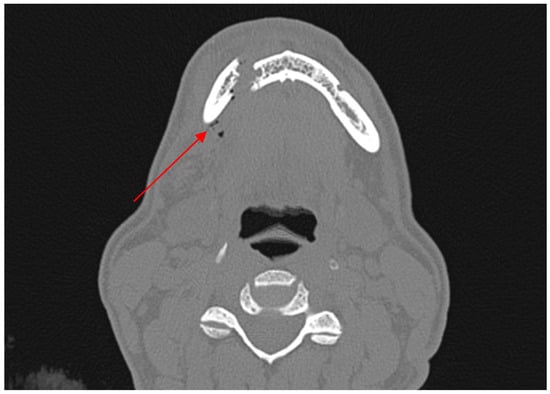

Diagnostic Utility of the “Air Sign” as a Radiological Indicator for Mandibular Body and Angle Fractures

- Gontarz, M.; Bargiel, J.; Gąsiorowski, K.; Marecik, T.; Szczurowski, P.; Zapała, J.; Wyszyńska-Pawelec, G. “Air Sign” in Misdiagnosed Mandibular Fractures Based on CT and CBCT Evaluation. Diagnostics 2024, 14, 362. [Google Scholar] [CrossRef]